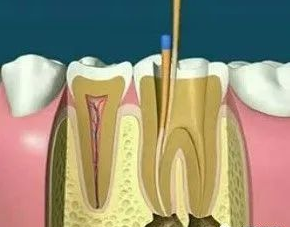

01、什么是根管調(diào)節(jié)?根管調(diào)節(jié),也稱為牙髓調(diào)節(jié),是調(diào)節(jié)牙髓疾病和根尖周疾病的有方法。通過去除根管中的炎性牙髓和壞死物質(zhì)并進(jìn)行適當(dāng)?shù)南荆畛涓芤韵軆?nèi)容物對(duì)根尖周圍組織的不利刺激,防止根尖周病變的發(fā)生或促進(jìn)根尖周愈合病變。此操作可保護(hù)牙齒,因此可與拔牙互補(bǔ)。根管調(diào)節(jié)很麻煩,通常需要2-4次就診才能完成,并且患者會(huì)遭受更多的痛苦。

02、根管調(diào)節(jié)的適應(yīng)癥牙髓炎:牙髓因細(xì)菌感染而發(fā)炎。在密封的牙髓腔中,牙髓通常不會(huì)被細(xì)菌感染。當(dāng)牙齒因齲齒而開孔時(shí),該孔太深,外部細(xì)菌會(huì)侵入牙髓腔,從而感染骨髓。根尖周炎:牙髓感染細(xì)菌后,細(xì)菌將通過根尖孔侵入牙槽骨,導(dǎo)致根尖周圍組織發(fā)炎。只要去除感染的牙髓,根尖的炎癥就會(huì)消退。牙髓裸露:當(dāng)牙齒折斷并且牙齒的神經(jīng)暴露時(shí),通常需要進(jìn)行根管調(diào)節(jié)。03、根管調(diào)節(jié)的步驟1、術(shù)前拍攝X線片:在根管調(diào)節(jié)過程中,在根管調(diào)節(jié)術(shù)前拍X線片,可以幫助診斷,了解髓室的位置和根管數(shù)目及形態(tài),測(cè)量根管工作長(zhǎng)度。

2、揭開髓腔:去凈腐質(zhì)和原有充填物、揭凈髓頂,看到整個(gè)髓底解剖結(jié)構(gòu)以便后續(xù)調(diào)節(jié)順利進(jìn)行。

4、根管預(yù)備:根管清理成形的目的是去凈根管壁上的感染物,通過根管器械的切削作用去除感染的牙本質(zhì)并清理根管壁細(xì)菌以利于根管充填。

5、根管沖洗、消毒:根管沖洗的目的是清除微生物、沖掉殘?jiān)瑵櫥芷餍岛腿芙庥袡C(jī)殘?jiān)?。然后,再進(jìn)行根管消毒,使根管內(nèi)達(dá)到無菌狀態(tài)。

6、根管充填:封閉整個(gè)根管系統(tǒng)、堵塞主根管和側(cè)副根管出口、防止微生物和液體的滲漏。無論是側(cè)方加壓法還是垂直加壓法,應(yīng)做到根管充填致密,根管充填后X線片上無根管腔隙,也不能超出根尖孔。